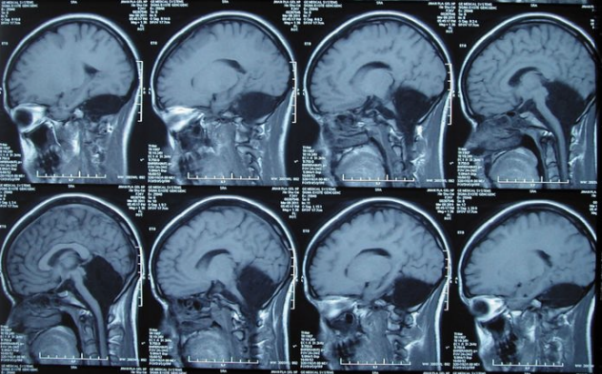

Normál agyi tomográfia, kisagy piros színben